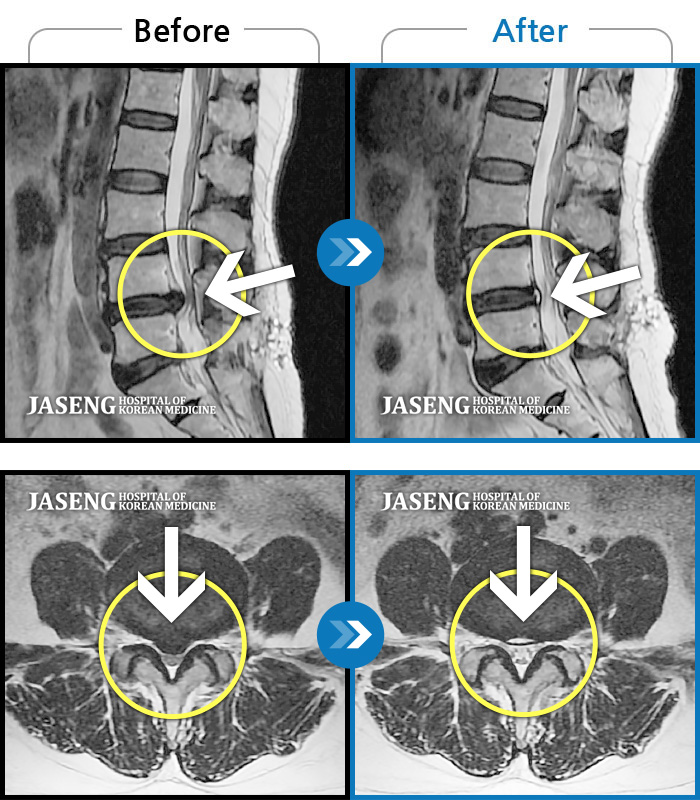

허리디스크

안산 · 김민수 원장

허리가 아프고 두 다리가 저려서 조금만 걸어도 주저 앉아야 했습니다.

촬영시기

2018.12.20 ~ 2023.02.21

2023.02.24

조회수 225